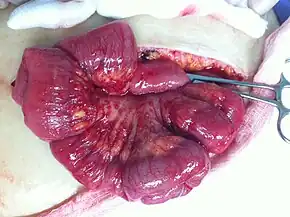

In advanced cancers, where complete removal is not an option, as much tumor as possible is removed in a procedure called debulking surgery. This surgery is not always successful, and is less likely to be successful in women with extensive metastases in the peritoneum, stage- IV disease, cancer in the transverse fissure of the liver, mesentery, or diaphragm, and large areas of ascites. Debulking surgery has usually only been done once[28] but a recent study has shown a longer overall survival in recurrent ovarian cancer when surgery combined with chemotherapy was performed compared to treatment with chemotherapy alone.[101] Computed tomography (abdominal CT) is often used to assess if primary debulking surgery is possible, but low certainty evidence also suggests fluorodeoxyglucose‐18 (FDG) PET/CT and MRI may be useful as an addition for assessing macroscopic incomplete debulking.[102] More complete debulking is associated with better outcomes: women with no macroscopic evidence of disease after debulking have a median survival of 39 months, as opposed to 17 months with less complete surgery.[26] By removing metastases, many cells that are resistant to chemotherapy are removed, and any clumps of cells that have died are also removed. This allows chemotherapy to better reach the remaining cancer cells, which are more likely to be fast-growing and therefore chemosensitive.[29]

There are several different surgical procedures that can be employed to treat ovarian cancer. For stage I and II cancer, laparoscopic (keyhole) surgery can be used, but metastases may not be found. For advanced cancer, laparoscopy is not used, since debulking metastases requires access to the entire peritoneal cavity. Depending on the extent of the cancer, procedures may include a bilateral salpingo-oophorectomy, biopsies throughout the peritoneum and abdominal lymphatic system, omentectomy, splenectomy, bowel resection, diaphragm stripping or resection, appendectomy, or even a posterior pelvic exenteration.[29]